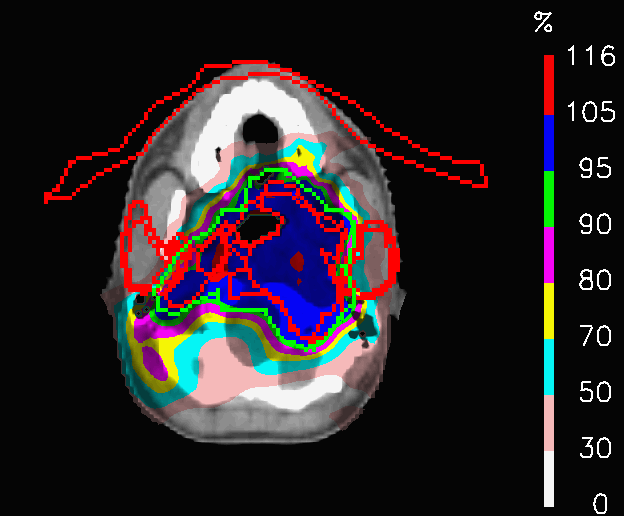

In PLAN-OL-2, a different field geometry has been investigated: the posterior fields are switched off at the level of the shoulders, the anterior ones at the level of the head and a fifth intracranial field is added (Fig.6). The goal was to achieve a better preservation of the OARs inside the head. The dose distributions (Fig.16) share a very similar coverage of the target volume, but they are characterized by substantial differences in the dose delivered to the OARs, as shown by Table 5. In fact, the huge improvements in the sparing of the chiasm, right lens (Fig.17a), left lens (17b), left inner ear and the spinal cord (considering in first place the decrease of 𝐃𝐦𝐚𝐱subscript𝐃𝐦𝐚𝐱\mathbf{D_{max}}) are followed by a significant increase of the peak dose inside the thyroid and the mean dose to the brainstem. In this case, PLAN-OL-2 is not necessarily superior to PLAN-NOM, but it is undeniable that the OL penalization has allowed the planner to test a scenario, that the simple enforcement of the dose constraints would not have provided.

Refer to caption

(a) Esophagus

(b) Spinal cord

Figure 16: Head and neck tumour: dose distributions of PLAN-NOM and PLAN-OL-2 at the level of the head.